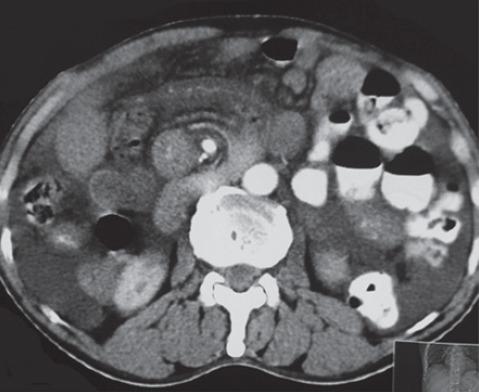

The incidence of the diverticulum of the small bowel varies from 0.2-1.3% in autopsy studies to 2.3% when assessed on enteroclysis. It occurs mostly in patients in the 6 decade of their life. Of all the small bowel diverticuli, jejunal diverticulum is the most common type. This rare entity is usually asymptomatic. However, they may cause chronic non-specific symptoms for a long period of time like dyspepsia, chronic postprandial pain, nausea, vomiting, borborgymi, alternating diarrhoea and constipation, weight loss, anaemia, steatorrhea or rarely lead to complications like haemorrhage, obstruction, perforation. Obstruction can be due to enterolith, adhesions, intussusception, and volvulus. The condition is difficult to diagnose because patients are generally presented with symptoms that mimic other diseases. It is important for clinicians to have awareness of this entity. Here, we present a case of multiple jejunal diverticuli with a history of repeated attacks of diverticulitis over past 20 years, which were misdiagnosed and now presented with intestinal obstruction due to volvulus of the involved segment along with mesentery around its axis. Resection of the diverticuli segment of jejunum was done with end-to-end jejuno-jejunal anastomosis. The patient is asymptomatic since 10 months of follow-up.

小肠憩室的发生率在尸检研究中为0.2%-1.3%,而在小肠灌肠检查时评估为2.3%。它大多发生在60岁左右的患者中。在所有小肠憩室中,空肠憩室是最常见的类型。这种罕见的病症通常无症状。然而,它们可能会长期引起慢性非特异性症状,如消化不良、慢性餐后疼痛、恶心、呕吐、腹鸣、腹泻与便秘交替、体重减轻、贫血、脂肪泻,或很少导致出血、梗阻、穿孔等并发症。梗阻可能是由于肠石、粘连、肠套叠和肠扭转引起的。这种病症很难诊断,因为患者通常表现出类似其他疾病的症状。临床医生了解这种病症很重要。在此,我们报告一例有20年反复憩室炎发作史的多发空肠憩室病例,该病例曾被误诊,现在因受累肠段连同其系膜围绕其轴扭转而出现肠梗阻。对空肠憩室段进行了切除,并进行了端端空肠吻合术。随访10个月以来,患者无症状。